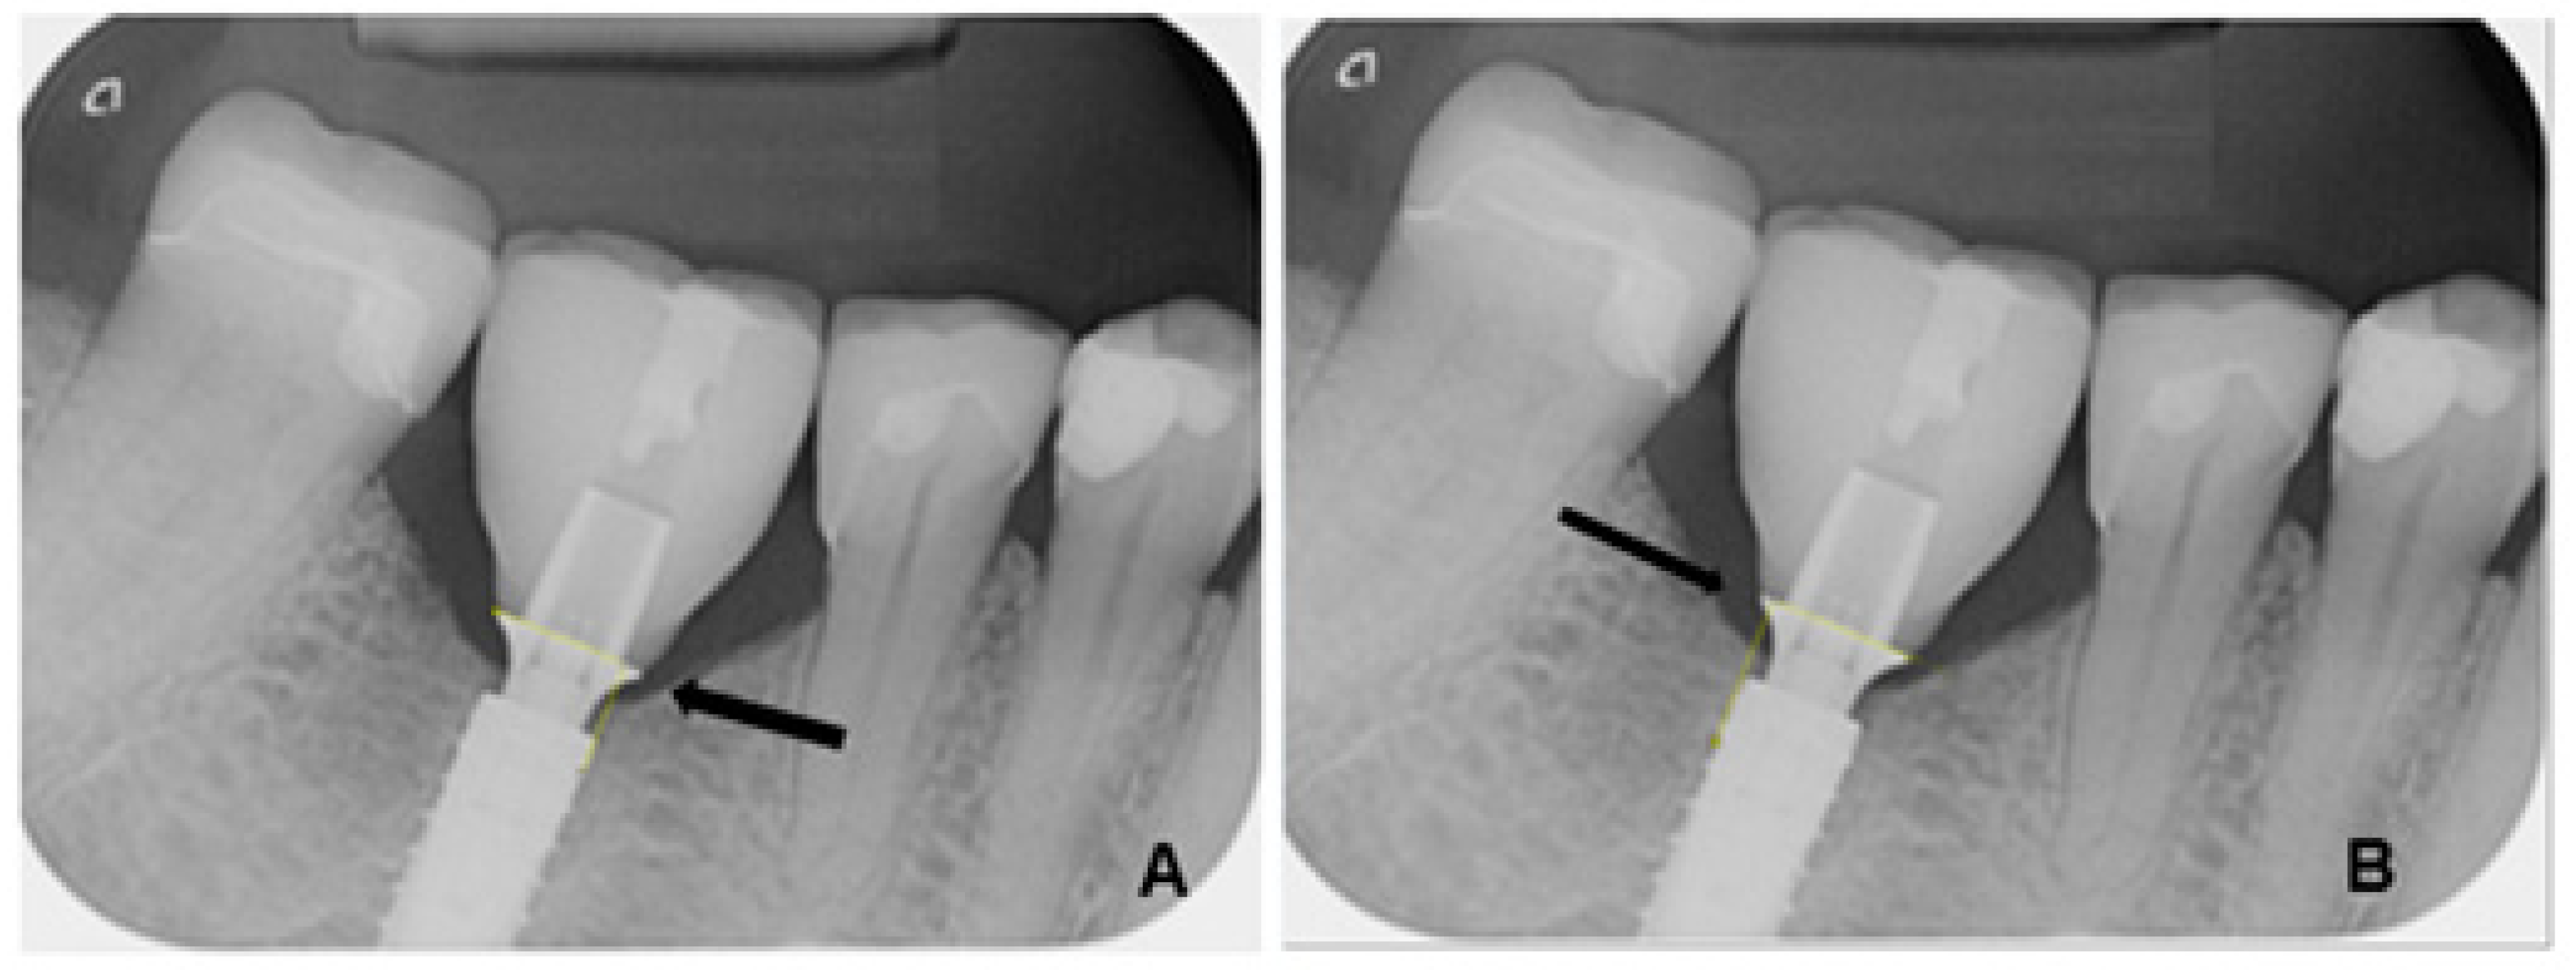

- Damage to the implant-abutment complex (Figure 2);

3.4. Technical Complications